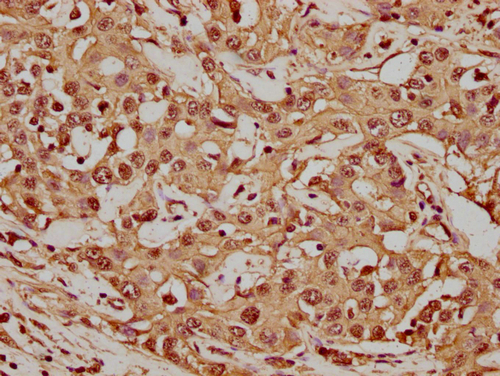

IHC image of CSB-PA010418PA56nme1HU diluted at 1:20 and staining in paraffin-embedded human colon cancer performed on a Leica BondTM system. After dewaxing and hydration, antigen retrieval was mediated by high pressure in a citrate buffer (pH 6.0). Section was blocked with 10% normal goat serum 30min at RT. Then primary antibody (1% BSA) was incubated at 4°C overnight. The primary is detected by a biotinylated secondary antibody and visualized using an HRP conjugated SP system.

IHC image of CSB-PA010418PA56nme1HU diluted at 1:20 and staining in paraffin-embedded human liver cancer performed on a Leica BondTM system. After dewaxing and hydration, antigen retrieval was mediated by high pressure in a citrate buffer (pH 6.0). Section was blocked with 10% normal goat serum 30min at RT. Then primary antibody (1% BSA) was incubated at 4°C overnight. The primary is detected by a biotinylated secondary antibody and visualized using an HRP conjugated SP system.